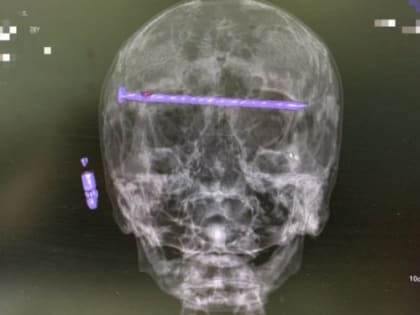

78-летний пациент в Нижнем Тагиле: врачи извлекли 15-сантиметровый гвоздь из головы

Сложнейшая операция спасла мужчине жизнь и зрение.